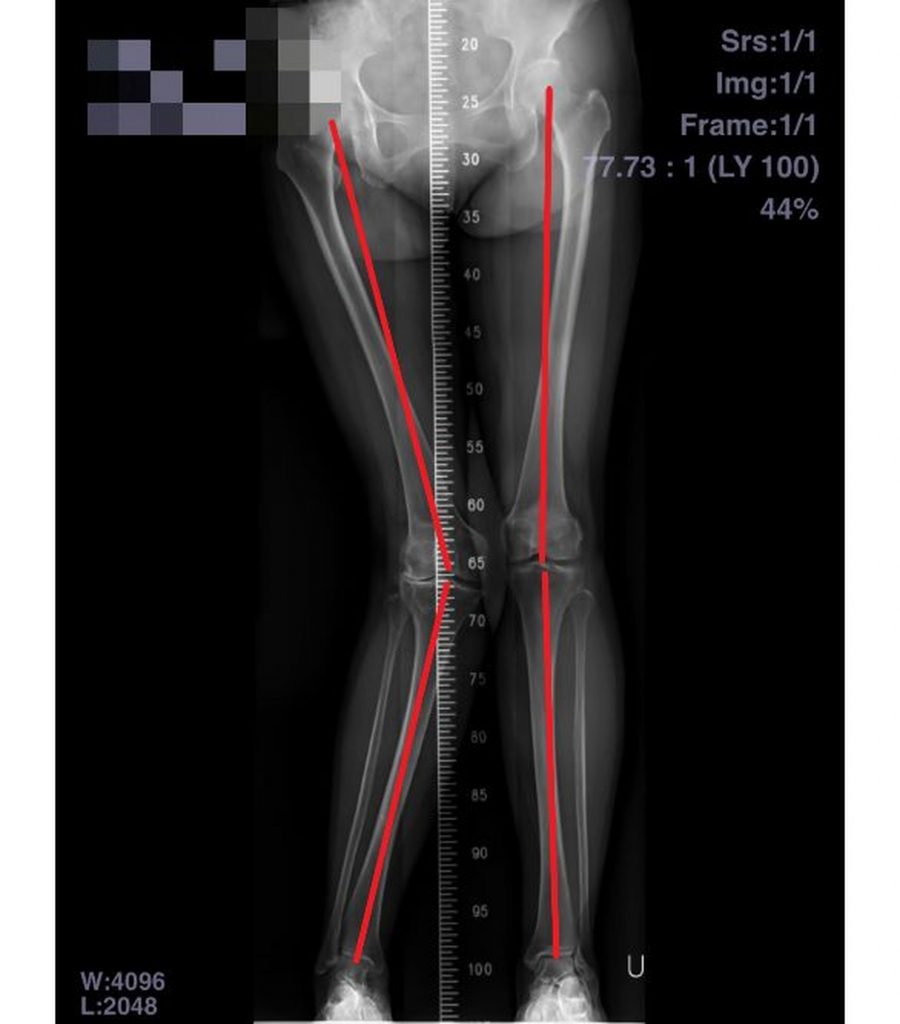

正常的雙腳於站立時膝蓋角度約5~7度,如大於10度則為膝外翻,依據角度大小分輕(小於10)、中(10~20度)及重度(超過20度)。許惟傑強調,人工膝關節置換術需評估遠端股骨和近端脛骨關節的截除角度、植入物軌跡與外轉角度等,憑技術與經驗判斷人工關節墊片厚度、置放位置,並依照關節部位承受壓力進行微調。且長期膝外翻也容易造成膝外側軟組織攣縮,伴隨不同程度上膝關節內側軟組織結構鬆弛,術後尚需配合復健來增強膝蓋力量,增加行走穩定度。